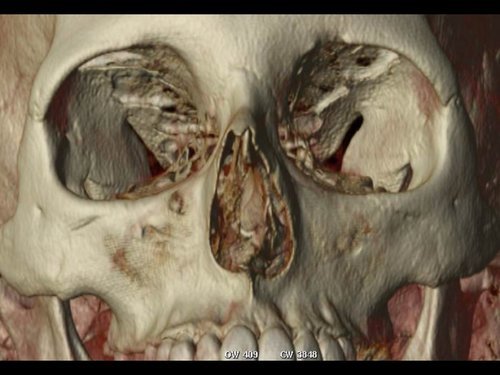

Depending on the shape of the septum, you may experience breathing difficulty on one or both sides of your nose. Some degree of septal deviation occurs in almost everyone. Reasons why more severe septal deviation can occur are related to abnormal growth, trauma or previous surgery. Symptoms such as difficulty breathing through the nose or intense snoring may indicate the need for a septoplasty. Deviation of the nasal septum frequently gives the nose a C-shape or crooked appearance, but occasionally the nose may appear straight while the septum deeper in the nose is deviated.

Dr. Derderian’s goal is to relieve the nasal airway obstruction caused by septal deviation and to refine the appearance of the crooked nose to look straight and natural. Septoplasty can be combined with cosmetic rhinoplasty procedures to improve the appearance of the nose further.

• During a septoplasty, Dr. Derderian removes abnormally curved bone and cartilage from the septum. He then repositions the nasal septum to the midline while using grafts from the removed portion of the septum to maintain the new straightened shape. He is usually able to work through incisions inside the nose, but it is occasionally necessary to make a small incision between the nostrils. Depending on the shape of the nasal bones, it may also be necessary to break the nasal bones so they can be repositioned. Repositioning of the nasal bones is very common in septoplasty performed to correct a crooked nose and deviated nasal septum due to trauma. Soft silicone splints are commonly placed in the nose after surgery to support the septum in its new position.